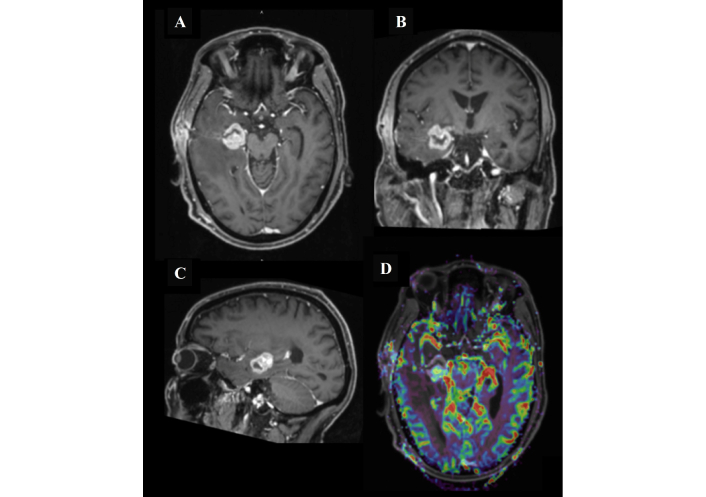

The patient underwent an initial stereotactic biopsy in November 2024 (Figure 2 is the post-operative MRI). A second biopsy was performed in December 2024 (Figure 3 is the post-operative MRI); however, both procedures were inconclusive, with histopathology demonstrating atypical lymphocytic proliferation with extensive necrosis. The first biopsy was (CD45+), and the second one immunohistochemical stains showed a positive cluster of differentiation 20 (CD20), paired box gene 5 (PAX-5), B-cell lymphoma 2 (BCL2), and multiple myeloma oncogene 1 (MUM1); CD10 and BCL6 were negative, and cellular myelocytomatosis oncogene (C-MYC) was equivocal. External pathological consultation failed to yield a definitive diagnosis. Given the ongoing clinical suspicion of PCNSL, he received a single cycle of R-MP (rituximab, methotrexate, procarbazine) chemotherapy on 21 January 2025 but subsequently developed methotrexate toxicity. Hepatitis B core antibody testing returned positive, and entecavir prophylaxis was initiated. During this period, the patient developed a left lower extremity deep vein thrombosis (DVT) and was started on therapeutic anticoagulation with enoxaparin, later transitioned to apixaban due to new-onset atrial fibrillation.

MRI of the head after the first surgical biopsy procedure. Follow-up magnetic resonance imaging (MRI) demonstrated a right medial temporal lobe lesion measuring 2.5 cm × 2.2 cm × 2.3 cm (anteroposterior × transverse × craniocaudal). The lesion shows intense post-contrast enhancement with an open ring configuration laterally (A, B, and C), corresponding to the stereotactic biopsy tract extending to the right temporal bone, accompanied by postoperative changes in the subgaleal soft tissues. There is extensive surrounding vasogenic edema with associated effacement of the right lateral ventricle. MR perfusion (D) demonstrates a mild elevation in cerebral blood flow, and MR spectroscopy reveals a relative increase in the choline peak. Additionally, bilateral periventricular and left subcortical T2/FLAIR hyperintense foci are noted.